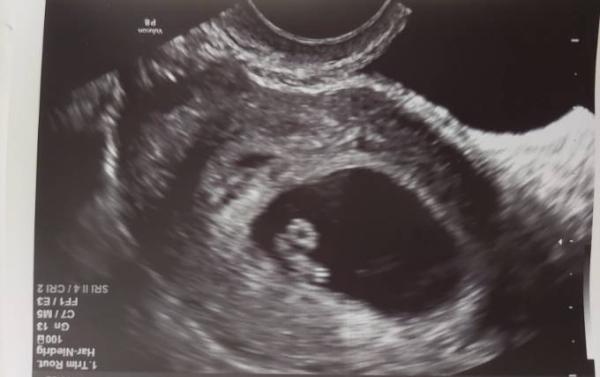

Hallo ihr lieben, Das Bild ist aus der 6 SSw. Mittlerweile bin ich schon weiter. Ich versuche mir aktuell die Zeit bis zum nächsten Ultraschall zu vertreiben, in dem ich mir verschiedene Geschlechterbestimmungstheorien ansehe. Dabei bin ich eben auch auf die Ramzi Theorie gestoßen. Hat jemand damit Erfahrung oder möchte sich mal an einer Auswertung probieren? Ich habs schon ausprobiert aber hätte gern mehrere Meinungen dazu. Ich würds auch auflösen, wenn ich von Frauenarzt irgendwann das Ergebnis habe, was es wird. Was meint ihr?

Bild ist von einem Vaginalen Ultraschall. Sollte ich vllt dazusagen